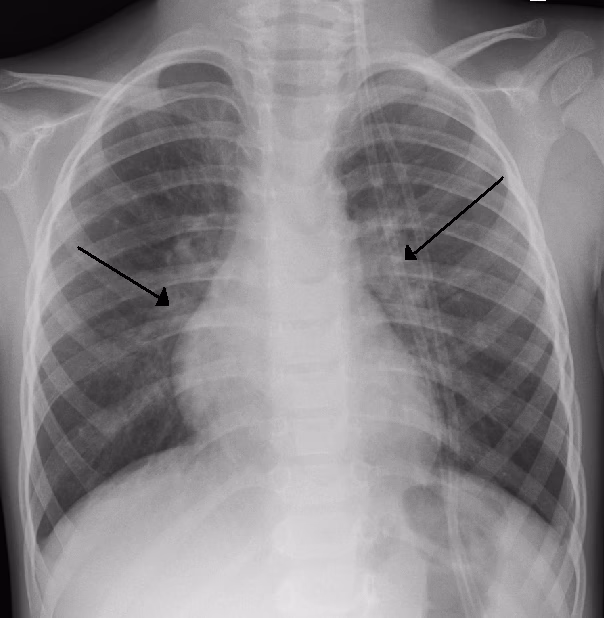

Lungebetændelse, eller pneumoni, er en infektion, der forårsager inflammation i lungeblærerne (alveolerne) i den ene eller begge lunger. Disse blærer kan blive fyldt med væske eller pus, hvilket gør det svært at trække vejret. Børn, især dem under fem år, er mere sårbare, da deres immunsystem stadig er under udvikling. Lungebetændelse kan være forårsaget af både vira og bakterier.

Symptomerne på lungebetændelse er typisk mere alvorlige end ved en almindelig forkølelse eller bronkiolitis. Barnet vil ofte have høj feber, føle sig meget sløjt og afkræftet (prostration) og have en dyb, produktiv hoste. Et af de mest tydelige tegn på lungebetændelse er anstrengt vejrtrækning. Man kan se, at barnet bruger mavemusklerne til at trække vejret, eller at huden trækkes ind mellem ribbenene eller ved halsen – dette kaldes indtrækninger.